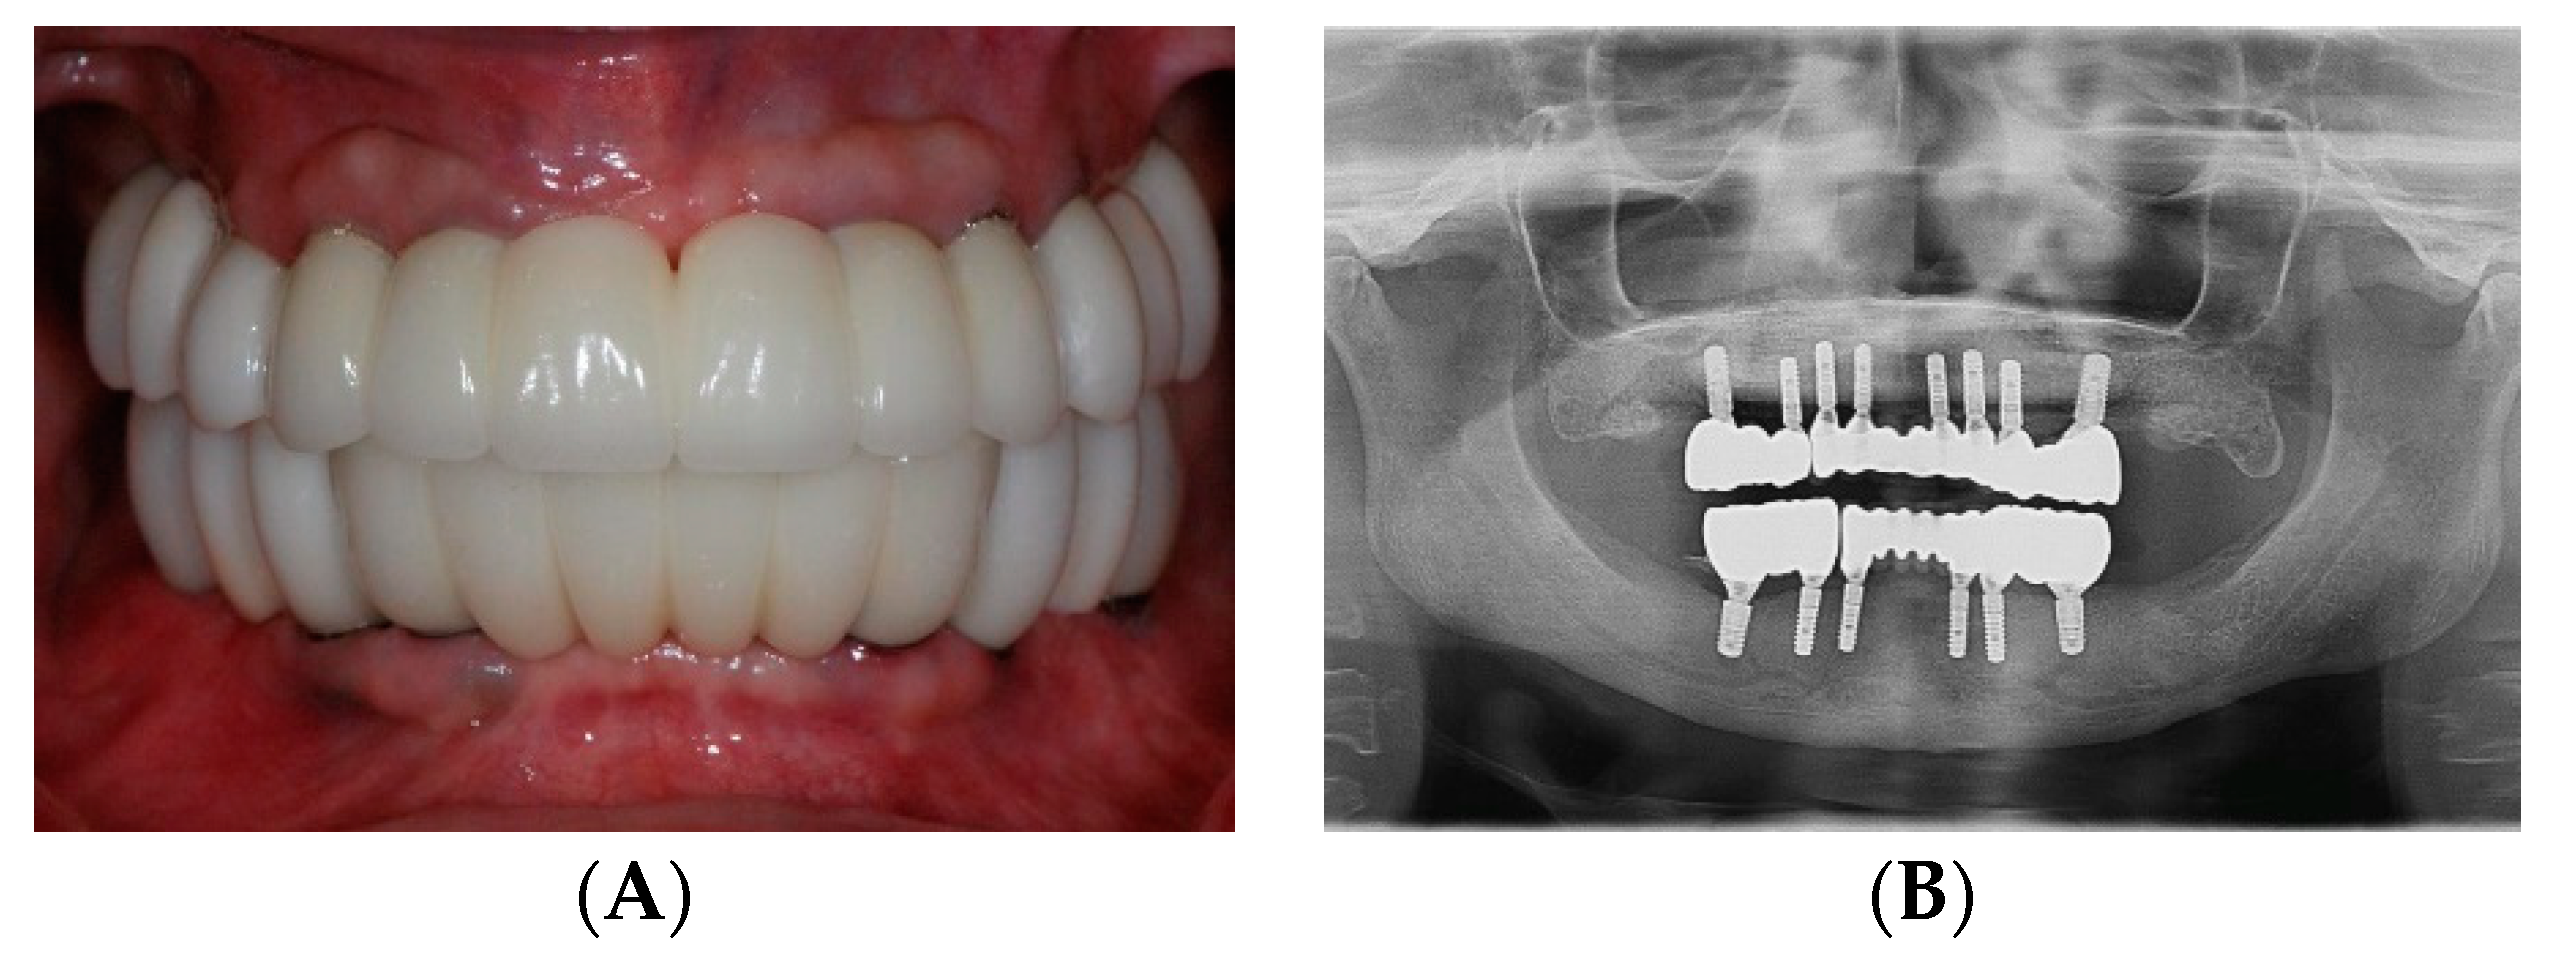

2.3. Surgical Phase: Virtual Planning of Implant Placement and Computer Guided Surgery

2.4. Restorative Phase: Second Strategic Extraction and Conversion of Provisional Prostheses with Integrated Digital Workflow